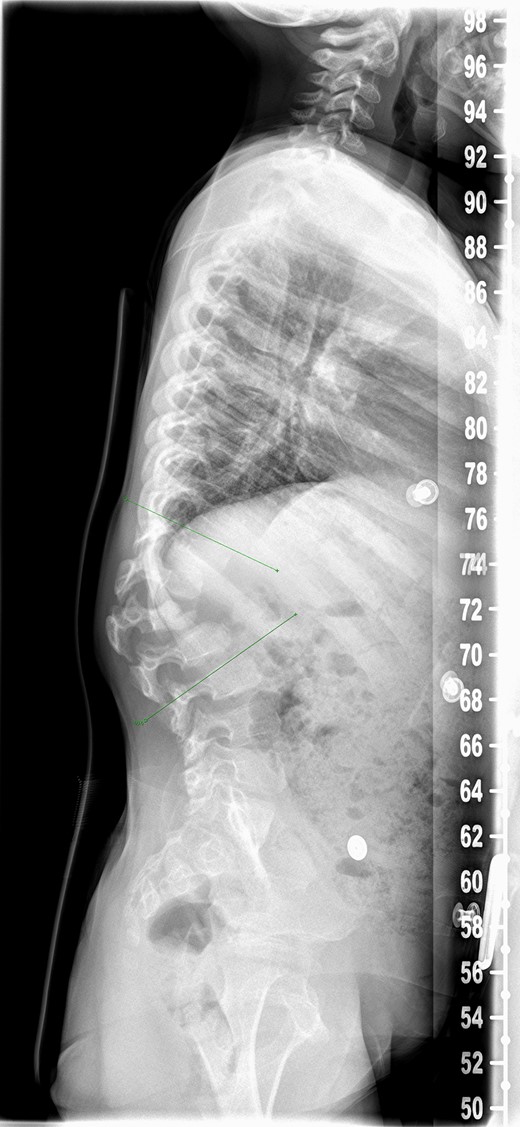

There was serous discharge with flakes of i-Factor in the drain postoperatively. Wound drain was removed on the second day and postoperative radiograph (Fig. 2) was satisfactory. Patient was discharged with a dry wound on the fifth day. Patient reattended hospital on seventh day with serous discharge from the drain site. There was no sign of infection and the wound was covered with a PICOTM dressing (Smith and Nephew), a negative pressure wound therapy system. At Day 10 the primary wound was healed, but serous fluid containing i-Factor flakes noted from the drain site. Patient was not started on antibiotics as there was no sign of infection and blood markers were normal. Wound was kept covered with a dressing and the discharge stopped.